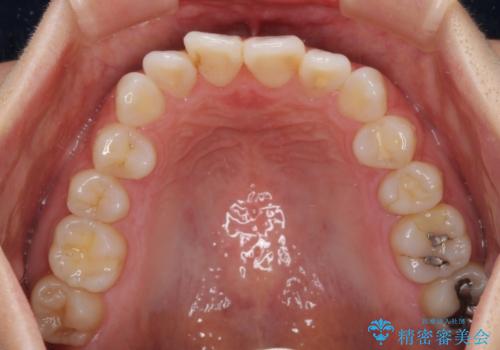

- ワイヤーではない矯正治療があると聞いたとのことで来院された患者様です。

長年前歯のデコボコを気にしていたもののワイヤー矯正に抵抗があり躊躇していたそうですが、インビザラインなら治療してみたいとのことで相談にいらっしゃいました。

インビザライン適用の歯列であったため、歯と歯の間を削るIPRを用いて改善することとしました。